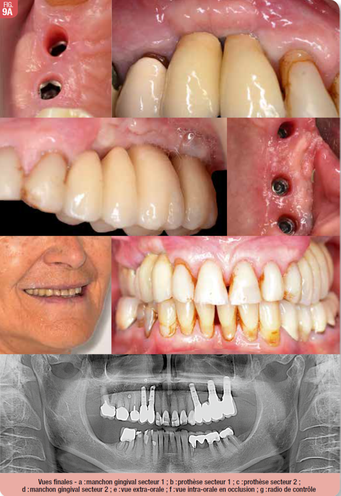

Phase prothétique

Les étapes de la phase prothétique sont réalisées classiquement pour deux bridge scellés (Fig. 10). La reconstitution comporte des couronnes solidarisées en 13-14 et bridge sur implants sur 24-25-26-27. L’occlusion est vérifiée en statique et dynamique. Le passage des brossettes est vérifié et validé avec la patiente : un espace est aménagé volontairement entre chaque implant pour un passage facilité. La patiente est revue régulièrement en contrôle et est satisfaite des résultats esthétiques et fonctionnels à 6 mois après la mise en bouche des prothèses.

Aménagement tissulaire muqueux

Le moment de l’aménagement des tissus mous péri-implantaires peut être débattu. S’il peut être réalisé dans le même temps que la pose implantaire (29), il est surtout intéressant en cas de greffe de conjonctif associée. Dans notre cas, la greffe osseuse secteur 1 et la hauteur d’os sous sinusienne limité secteur 2 requéraient une mise en nourrice des implants. La gestion des tissus mous pouvait donc être effectuée lors de la mise en place des vis de cicatrisation. L’intervention a consisté en un déplacement apical de la gencive kératinisée sans apport de greffon gingival. Cet aménagement a permis l’obtention d’une hauteur de gencive kératinisée supérieure à 2mm, suffisante pour assurer la pérennité implantaire (30).